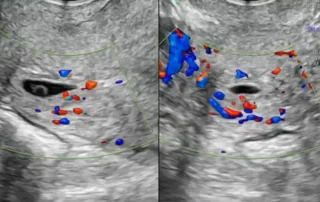

DOI: 10.36205/trocar7.2026008 - Real-Time Surgical Guidance with Robotic-Integrated Intraoperative Ultrasound in Bowel Endometriosis: A Two-Case Experience

Anshuma Shukla Kulkarni, Anushka Mehta, Riyanshi Thakur

Real-Time Surgical Guidance with Robotic-Integrated Intraoperative Ultrasound in Bowel Endometriosis: A Two-Case Experience

DOI: 10.36205/trocar7.2026009